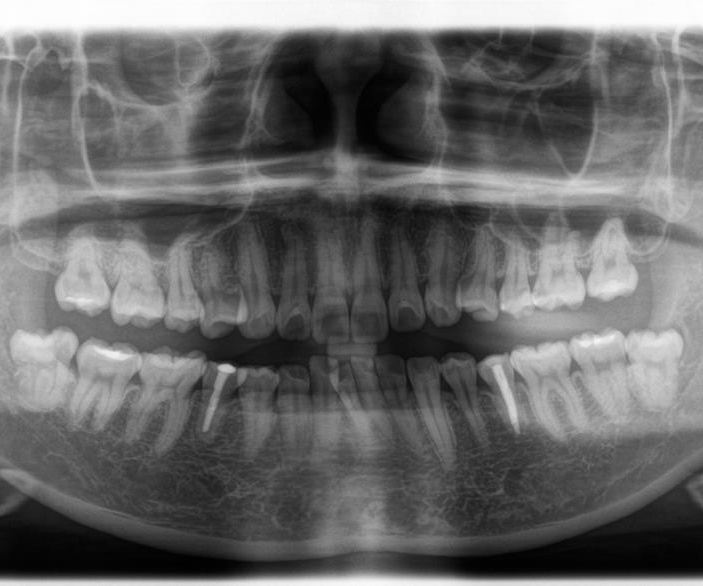

インプラント  歯科用のインプラントは、スウェーデンの整形外科医であるブローネマルク教授が実験中に骨とチタンが外れなくなったことことから発展してきました。現在のインプラントは乳歯、永久歯に続く第3の歯と呼ばれ、義歯やブリッジにはないたくさんの恩恵を享受することができる反面、トラブルも多数報告されています。インプラントが自分の歯を超えることは、未来永劫あり得ません。治療にはメリットだけではなくデメリットもありますので、よく相談してインプラント治療を行うのが良いと思います。 当院ではスウェーデン、アストラテック社のインプラントを採用しております。長期的に良好な治療成績を有する優れたインプラントです。骨がなくてインプラントができないと言われた方もご相談ください。